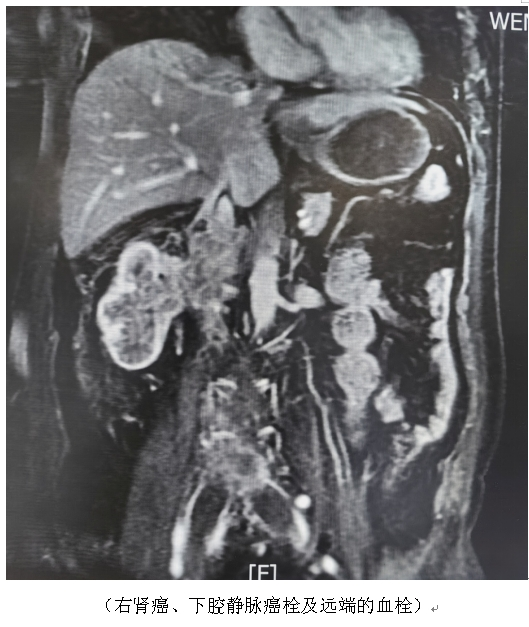

患者,男性,65岁,此次因“突发昏厥10小时”被送到我院急诊,拟急性肺动脉栓塞急诊入住血管外科,郑祥韬主任团队予以紧急实施肺动脉吸栓和下腔静脉滤器植入,病人迅速转危为安。病情平稳后,经过进一步检查发现,该患者肺动脉栓塞的真正根源是,右侧巨大肾癌合并下腔静脉癌栓,癌栓的近端接近了第二肝门,远端静脉管腔内继发了大范围的血栓形成,甚至达到两侧髂总静脉。幸运的是,该患者PET-CT检查未发现其他远处的转移灶。

肾癌是泌尿系统最常见的肿瘤之一,局部进展期肾癌中4-10%合并下腔静脉癌栓,甚至蔓延至心房和肺动脉,未经治疗的肾癌合并下腔静脉癌栓患者自然病程短,预后差。手术切除,对于大多数患者来说是最有效的治疗方式。肾癌根治性切除联合腔静脉瘤栓取出术是公认的泌尿外科顶尖的高难度手术,被称之为“皇冠上的明珠”,需要术者具有高超的手术技巧与过硬的心理素质,高位癌栓的处理还需要心脏外科、血管外科、肝胆外科以及麻醉科、手术室、重症医学科等相关科室的共同协作,手术过程中面临许多难点、风险和挑战,例如术中癌栓脱落、大量出血、巨大肾肿瘤导致腹腔内解剖异常、高位的癌栓需要心脏停跳体外循环等,以上问题如有处置不当,可能会引起严重的并发症直接危及生命。我院今年经治的这两例患者都是因为急性肺梗塞被发现,围手术期需要使用足量的抗凝药物,让手术操作和术后的管理难上加难,该手术的顺利开展,真正反映了我院多学科团队合作对危重疾病的综合救治能力和水平。